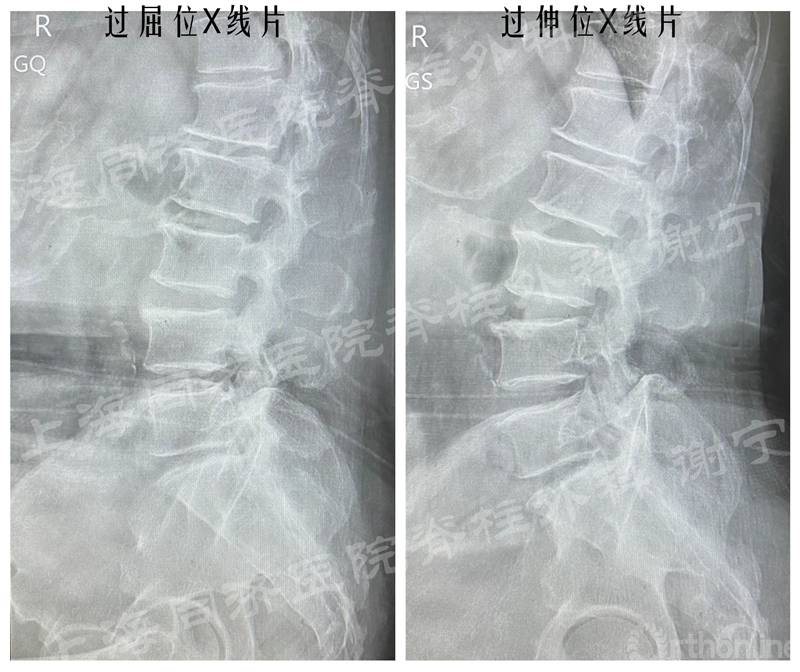

患者男性,66岁,左下肢疼痛麻木2月余,加重3周入院。左直腿抬高征阳性。X线片示腰椎轻度侧弯,未见明显不稳。MR和CT示L5/S1椎间盘脱出,椎间盘合并骨化,中央偏左侧。

图11 术前X线片